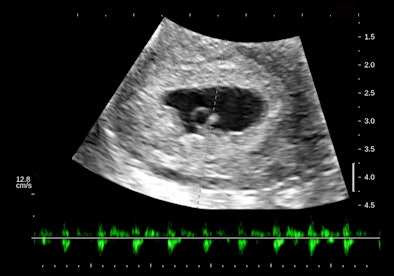

There is a intrauterine pregnancy with a (right) corpus luteum with an intact vascular margin. A regular heart rate of 122 beats per minute implies a 6.0-week stage. The Doppler pattern has separate filling and ejection phases. The decidual boundary is thick and well implanted. But there was another unexpected finding when looking at the left ovary:

![]() |

The findings in these views of the distal descending left colon are typical and classic for active ulcerative colitis. The submucosa is thick, reflective, and hyperemic. Some divots can be seen along the mucosa and one transverse section shows a tiny submucosal cyst. What do you think a transabdominal exam would have shown? Would that study have served the best needs of this patient?